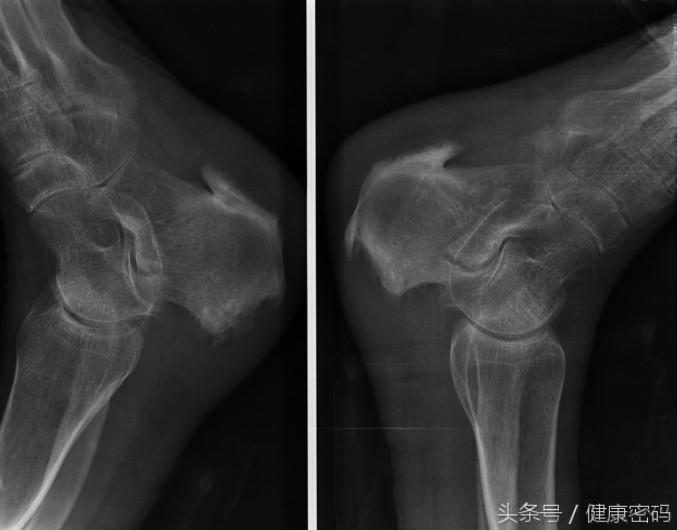

关于骨刺,病因可能来自从小到大的跌倒与碰撞,也可能是长时间久坐久站或姿势不良所引起。之所以难以处理,跟个人习惯有很大的关系,初期只有偶发性的酸胀麻痛,很多人因此不以为意,长期下来身体会慢慢习惯这些错误的姿势或不明显的酸痛,在我们不注意的时候,椎间盘有可能已经受到潜在性伤害或小破裂。等到年纪稍长,骨骼强度退化;又或是长期的压力累积,使肌肉层失去弹性,降低对脊椎的保护力时,情况便会持续恶化成椎间盘突出、骨刺、坐骨神经痛等病果。

还记得当时他已被确诊为骨刺,长期的疼痛让身为公务员的他坐立难安,过在之前也仅是消极的定期回诊,透过药物抑制疼痛感,最后直到左脚也因神经被压迫而常常发麻、难以动弹之时,他才惊觉事态严重。